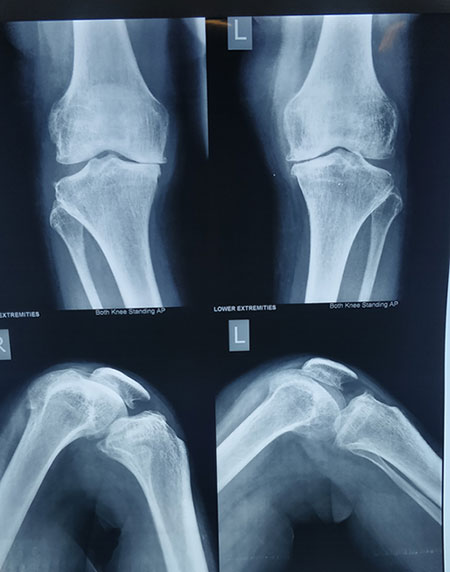

STEPS OF HTO